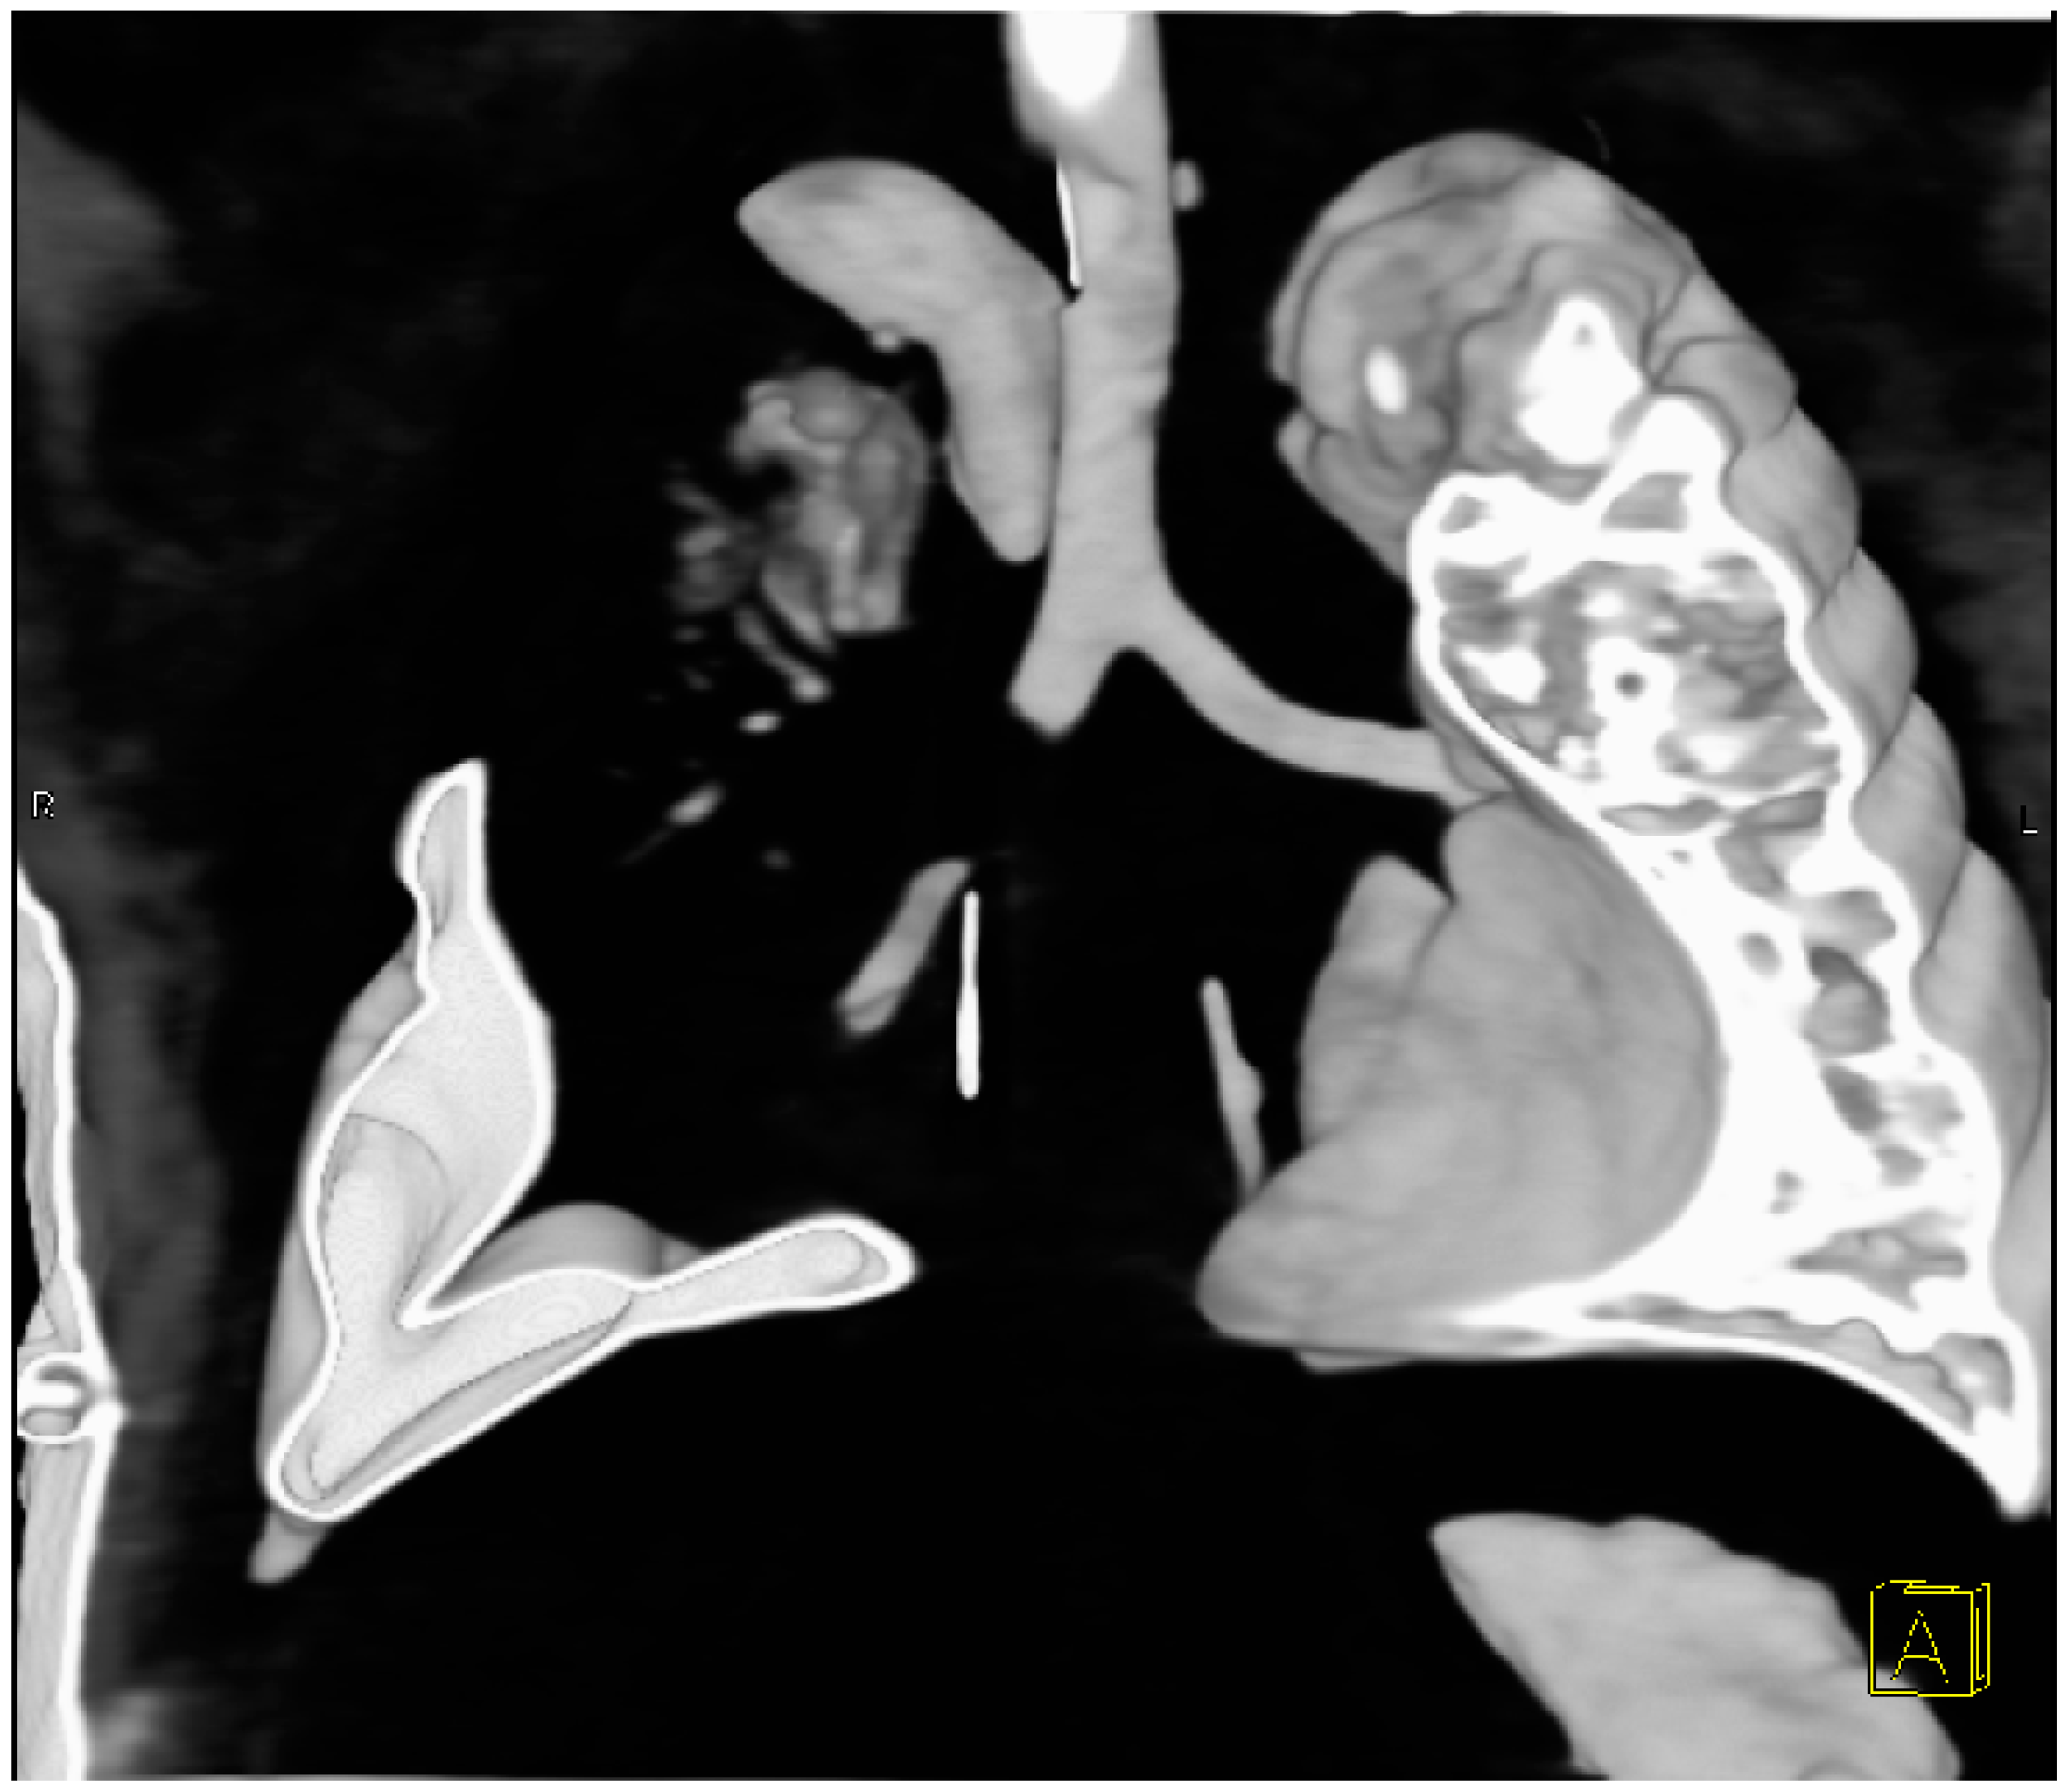

2. Case Presentation

2.2. Surgical Intervention